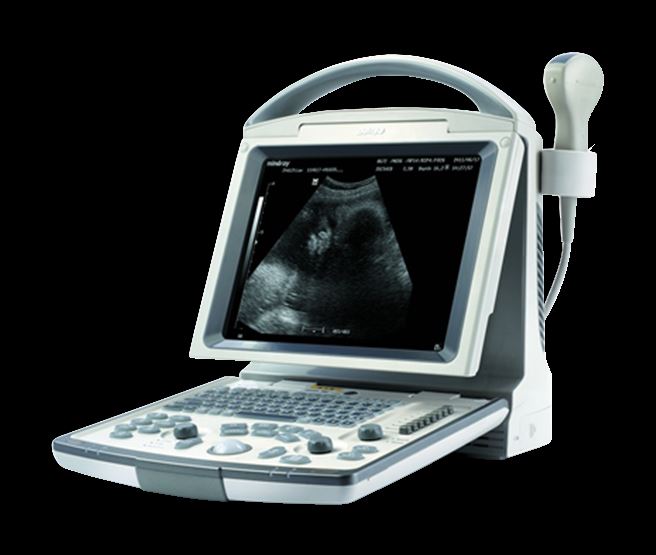

DIAGNOSTIC ULTRASOUND MACHINES FOR SALE

MindRay Diagnostic Ultrasound System DC7

Sale price$ 39,487.99

Save $ 700.00